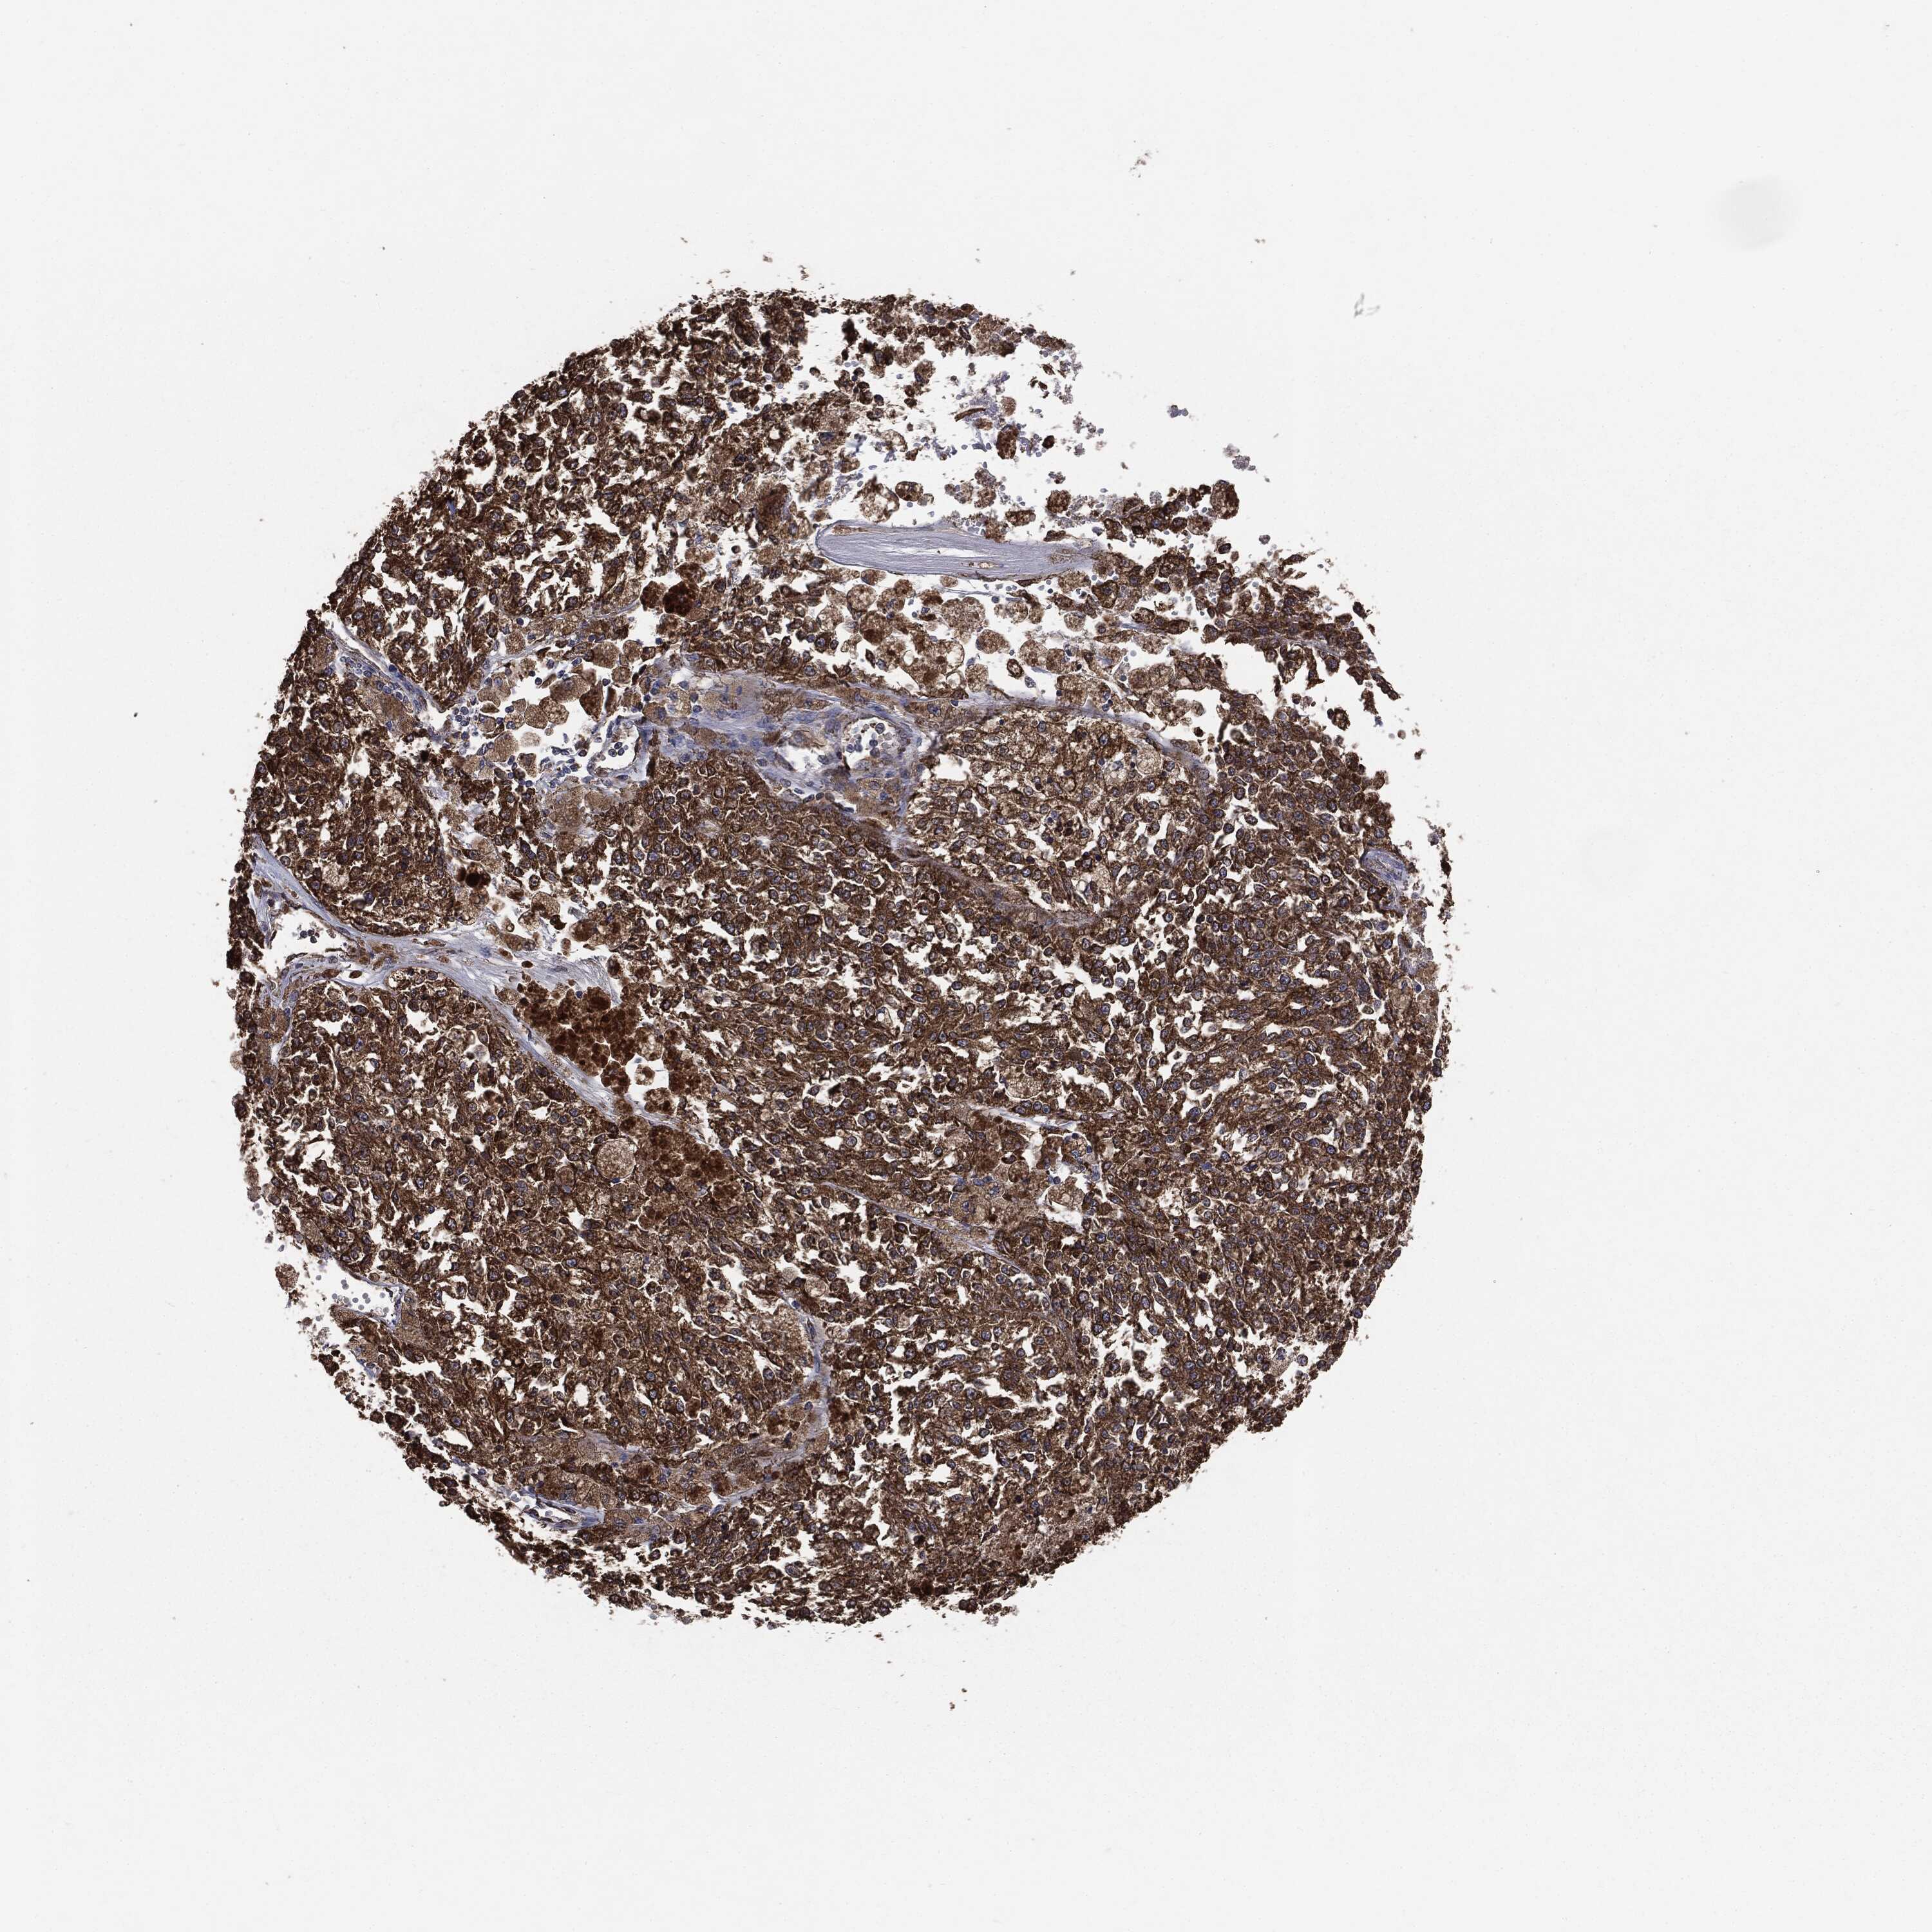

MELANOMA - Protein expressioni

A mouse-over function shows sample information and annotation data. Click on an image to view it in a full screen mode. Samples can be filtered based on level of antibody staining by selecting one or several of the following categories: high, medium, low and not detected. The assay and annotation is described here.

Note that samples used for immunohistochemistry by the Human Protein Atlas do not correspond to samples in the TCGA dataset.

Antibody stainingi

Antibody staining in the annotated cell types in the current human tissue is reported as not detected, low, medium, or high, based on conventional immunohistochemistry profiling in selected tissues. This score is based on the combination of the staining intensity and fraction of stained cells.

Each image is clickable and will lead to virtual microscopy that enables deeper exploration of all samples and also displays staining intensity scores, fraction scores and subcellular localization as well as patient and tissue information for each sample.

CAB069425

CAB080053

CAB080065

CAB080070

CAB080081

CAB080095

CAB080097

Staining

High

Medium

Low

Not detected

Intensity

Strong

Moderate

Weak

Negative

Quantity

>75%

75%-25%

<25%

None

Location

Nuclear

Cytoplasmic/membranous

Cytoplasmic/membranous,nuclear

Malignant melanoma, NOS

Malignant melanoma, Metastatic site